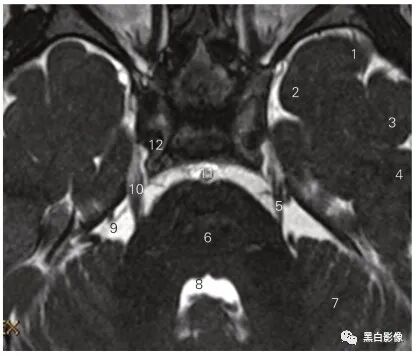

图5-3 经视交叉和垂体柄的冠状断层MR T1加权图像

1 尾状核 caudate nucleus 2 岛叶 insular lobe

3 视交叉 optic chiasma 4 动眼神经 oculomotor nerve

5 颈内动脉 internal carotid artery 6 侧副沟 collateral sulcus

7 颈内动脉 internal carotid artery 8 垂体 hypophysis

9 垂体柄 manubrium of hypophysis

10 大脑中动脉 middle cerebral artery 11 壳 putamen

12 内囊前肢anterior limb of internal capsule

13 透明隔 septum pellucidum

14 胼胝体干 trunk of corpus callosum